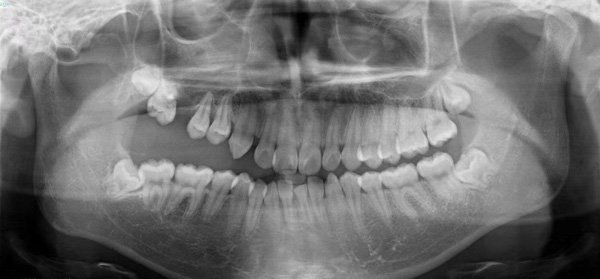

患者小潘(化名)是一名花季少年,5年前發(fā)現(xiàn)右側(cè)牙齒無法咬合,隨著年齡的增長(zhǎng),癥狀越來越嚴(yán)重,遂來到柳州市人民醫(yī)院口腔科就診,經(jīng)仔細(xì)檢查,確診為右側(cè)先天性頜骨畸形伴有上頜牙列缺損。

“上頜骨作為面中部1/3的骨性支撐,不僅決定了面中部的突度,還對(duì)患者的露齒、上牙中線的偏斜、牙合平面的偏斜等產(chǎn)生影響。”據(jù)口腔科副主任醫(yī)師劉彥杰介紹,該患者右側(cè)面部較左側(cè)面部較小,右口角向上歪斜,右上唇較左側(cè)薄,口內(nèi)咬合紊亂,右側(cè)開牙合,右上頜高出頜平面3-5cm,右下頜舌傾。如果不加以干預(yù),可能會(huì)造成咬合紊亂加劇,面部愈發(fā)不對(duì)稱,甚至累及顳下頜關(guān)節(jié)導(dǎo)致顳下頜關(guān)節(jié)紊亂,最終影響面部頜口腔功能,進(jìn)食說話都受到影響。